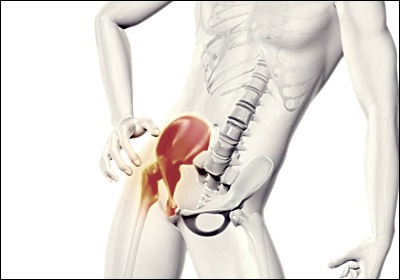

고관절의 구조와 기능

고관절은 우리 몸에서 가장 큰 관절 중 하나로, 대퇴골 머리와 골반의 비구가 만나는 부위입니다. 이 관절은 체중을 지탱하고 보행, 달리기, 점프 등 다양한 움직임을 가능하게 합니다. 고관절은 활액막, 연골, 인대 등으로 구성되어 있으며, 이들이 조화롭게 작용하여 부드러운 움직임을 가능케 합니다. 하지만 이러한 구조물 중 어느 하나라도 문제가 생기면 통증이 발생할 수 있습니다. 고관절의 정상적인 기능은 우리의 일상생활과 신체 활동에 매우 중요하므로, 이 부위의 건강을 유지하는 것이 필수적입니다.